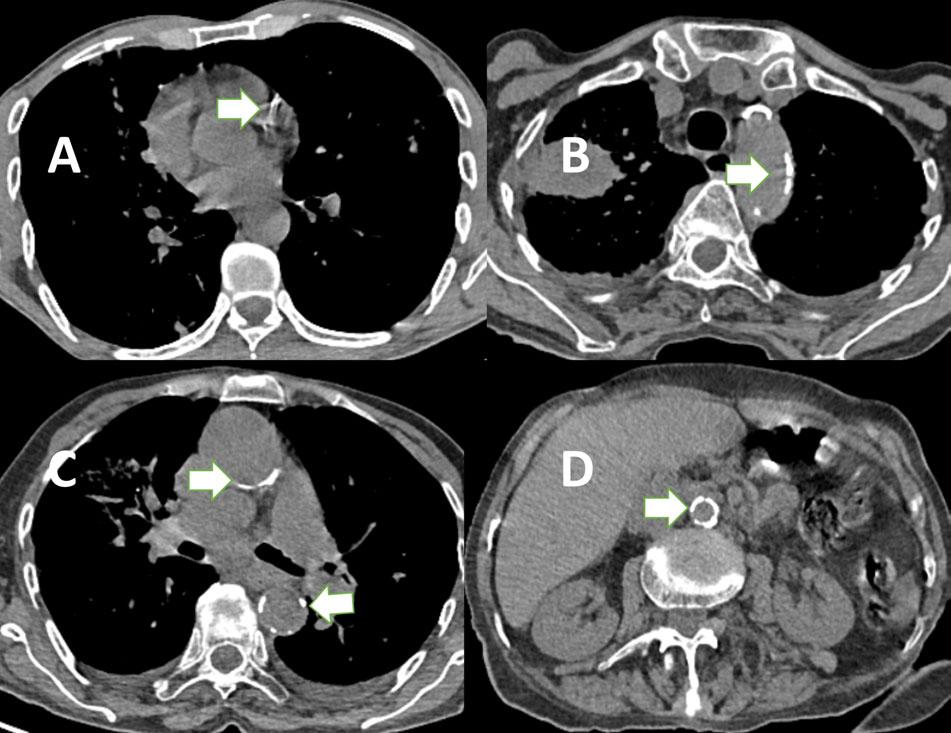

Table 8 shows the sensitivity, specificity, Positive Predictive Value (PPV) and negative predictive value of AoC in predicting CAC. It is evident from the table that though the sensitivity of arch of aorta calcification in predicting CAC detecting is higher than any other part of aorta, but presence of both thoracic & abdominal aorta is 92.7% sensitive in predicting CAC. In contrast, the specificity is highest with descending thoracic aorta being 93.8%. Though the highest PPV of 70.7% was achieved with combined thoracic & abdominal AoC but the NPV of all parts of aorta is equal & higher ie, 90.4%. The overall accuracy of AoC for predicting CAC was with descending (DSN) AoC being 85.6% followed by abdominal AoC being 80.6% (Fig 1).

Fig 1(A-D) — Axial Noncontrast Computed Tomography (NCCT) Images of Thorax (A-C) and Abdomen (D) show Coronary Artery Calcification (A), Aortic Arch Calcification (B), Ascending & Descending Thoracic Aorta Calcification (C), & Abdominal Aorta Calcification (D) in different patients (arrows).